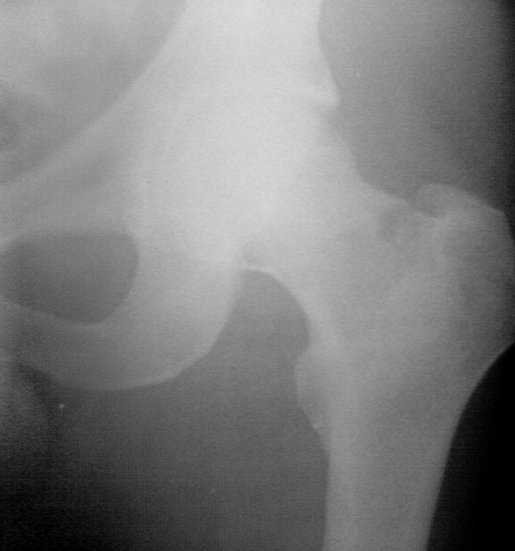

Перелом шеки бедра у Вашего пациента благоприятный - основание шейки бедра.

В отличии от трансцервикального или субкапитального вероятность развития аваскульрного некроза относительно низкая т.к. кровоснабжение головки бедра по ретинакулярным сосудам сохранено. Фиксация трехлопастным гвоздем не эффективна т.к. гвоздь да и шурупы не обеспечивают угловой стабильности. Кроме этого, техника установки трехлопастного гвоздя может повредить оставшиеся целыми ретинакулярные сосуды. Наиболее подходящие фиксаторы должны иметь фиксированый угол - шуруп с диафизарной пластинкой типа DHS или любой интрамедуллярный гвоздь имеющий блокирующие шурупы которые можно ввести в шейку бедра типа PFN, Reconstruction nail, Gamma или др. Скелетное вытяжение тоже может сработать, только, конечно, значительно труднее достичь редукции и опять же при перерастяжении возможно нарушение кровообращения головки бедра.

В отношении угловой стабильности. Я напоминаю, что мы говорим о переломе в основании шейки бедра. При введении гвоздя или шурупов есть только одна опорная точка на наружном кортксе. Нагрузка на головку бедра вращает весь проксимальный фрагмент на варус вокруг этой точки без всякой помехи.

Для сохранения редукции необходима жесткая угловая фиксация.